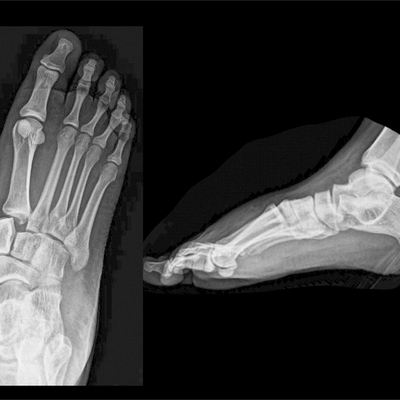

Click on an image below to view more info.